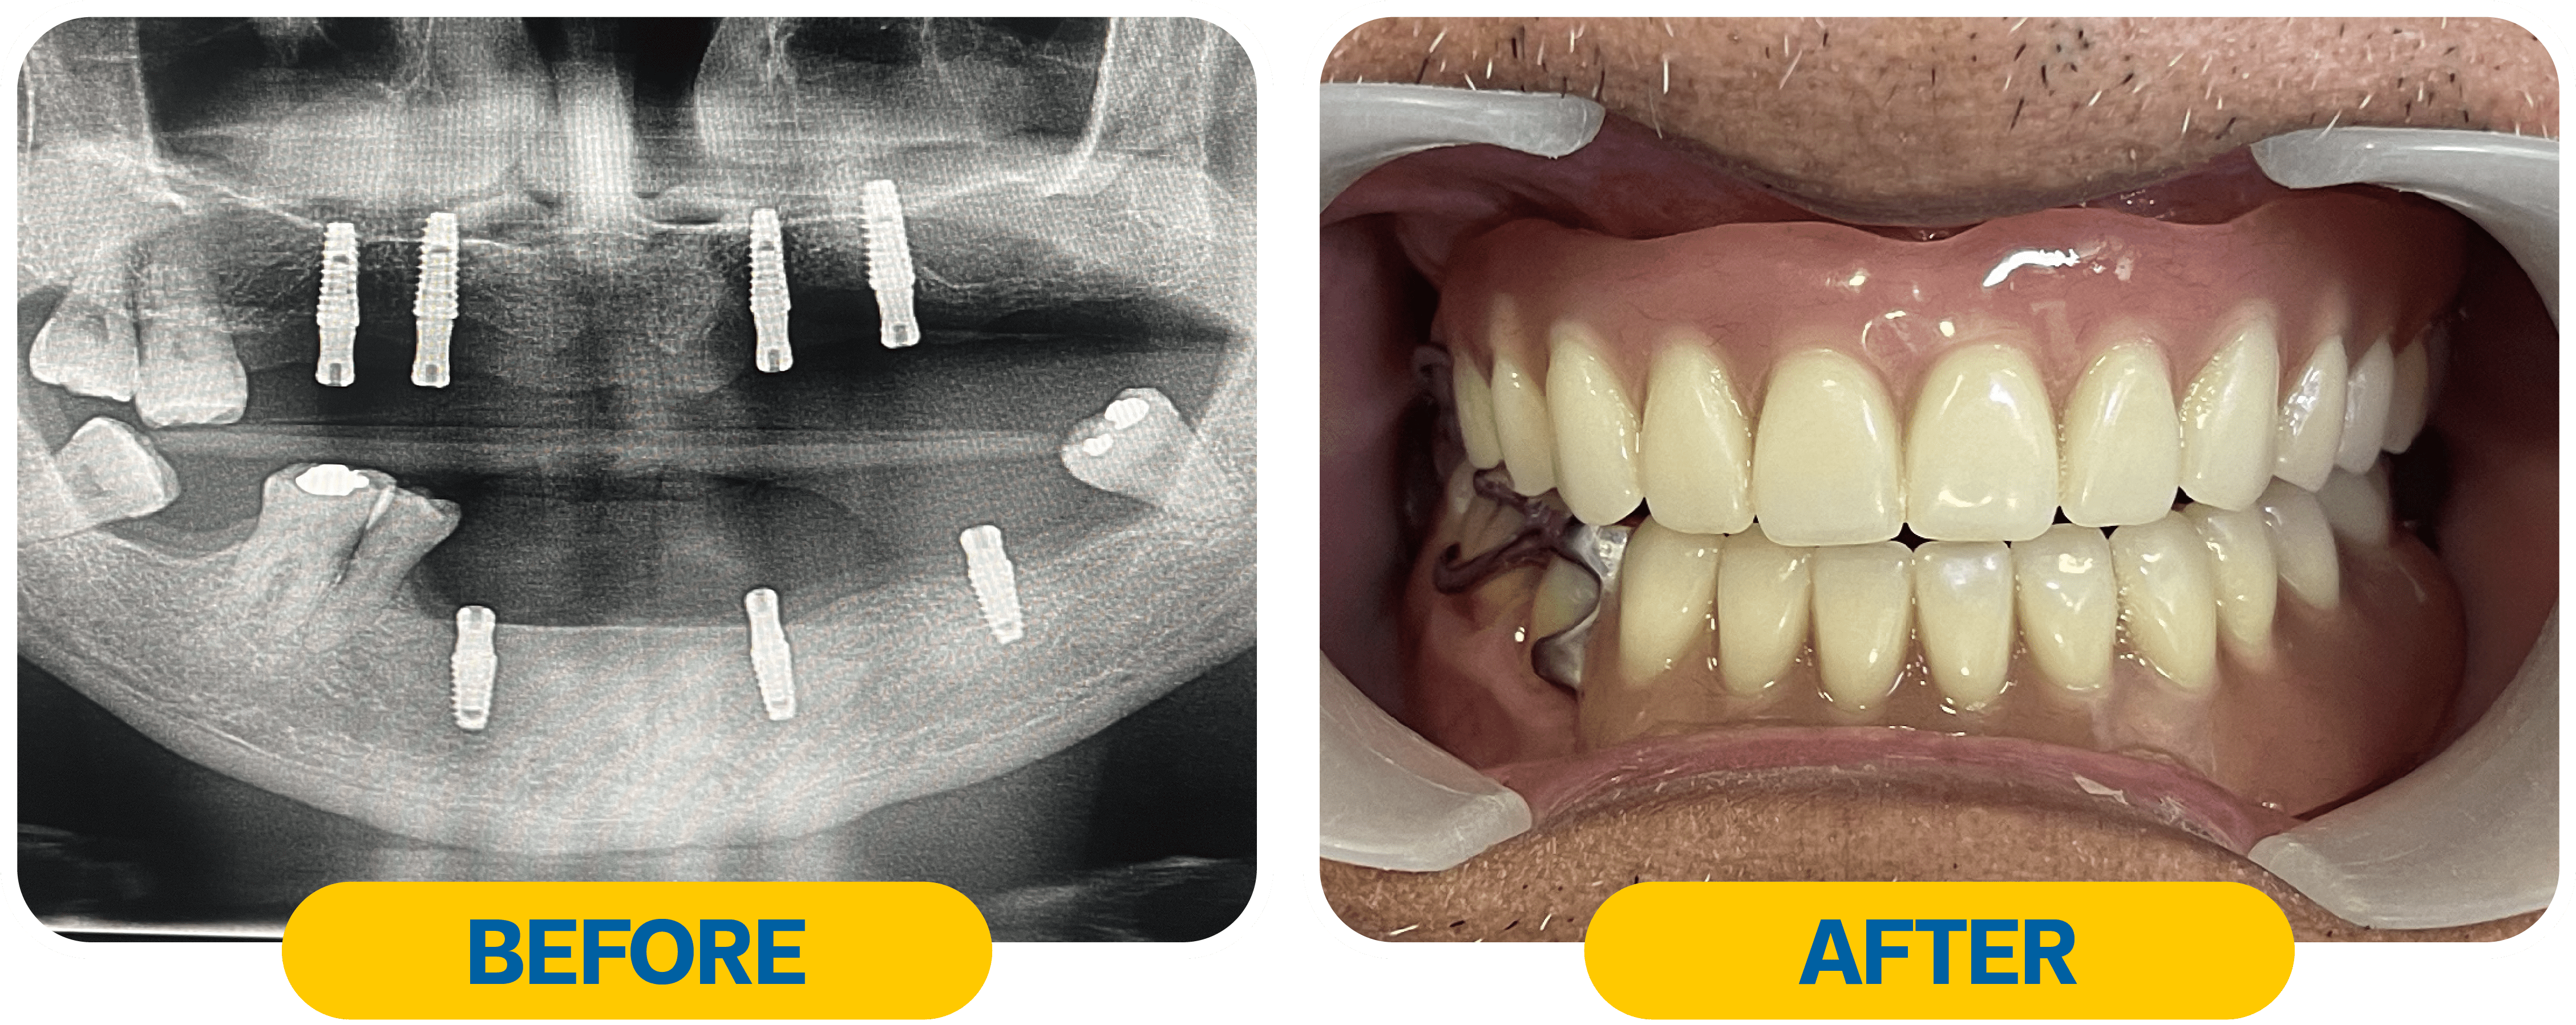

รีวิวเคสฟันปลอมแบบใช้รากฟันเทียมเสริม